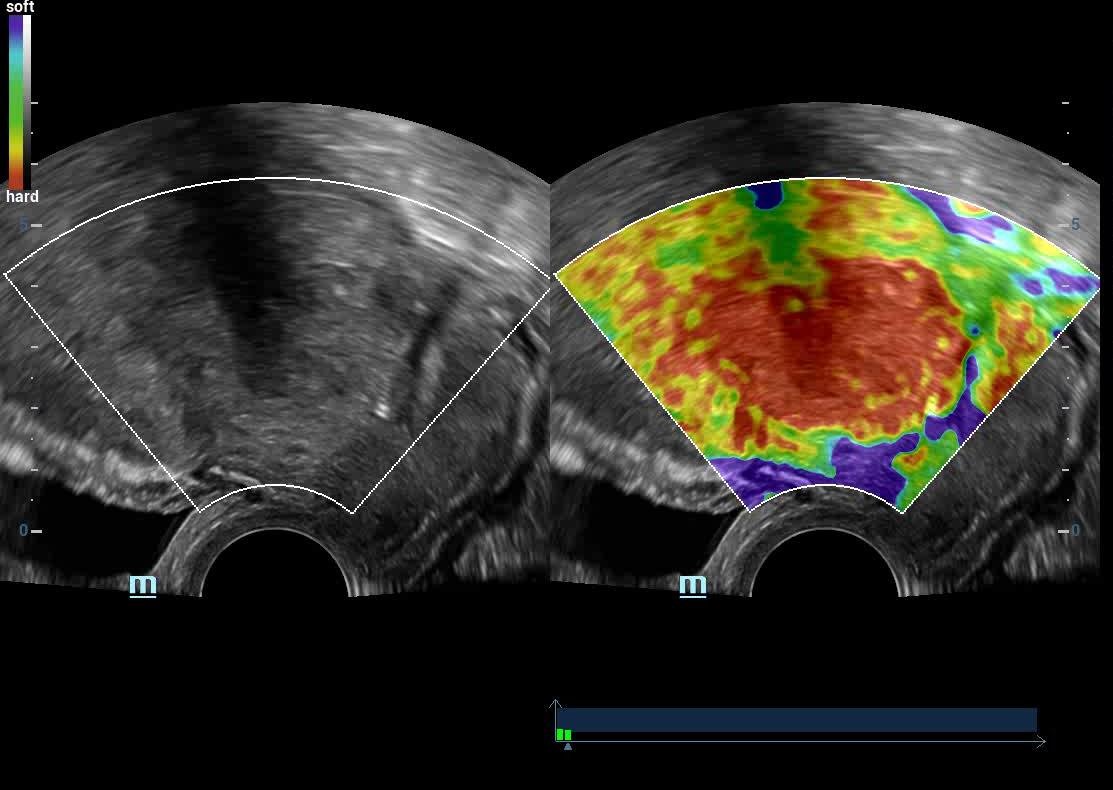

• Shear Wave Elastograghy & Strain Elastography

• High End SHEAR WAVE ELASTOGRAPHY For LIVER FIBROSIS/THYROID MALIGNANCY/BREAST CANCER

Liver Elastography